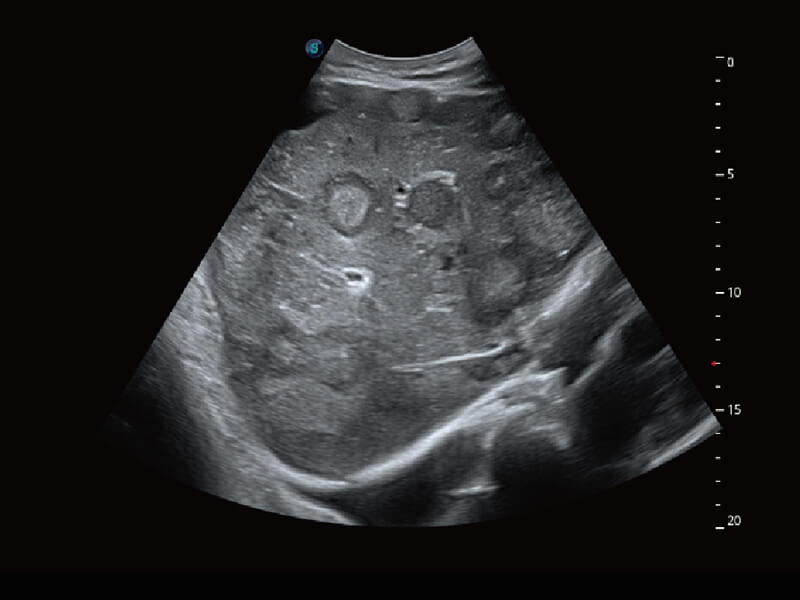

S-Fetus 产科扫查助手

• 缩短

操作时间

• 提升

准确率

• 单次

按键操作